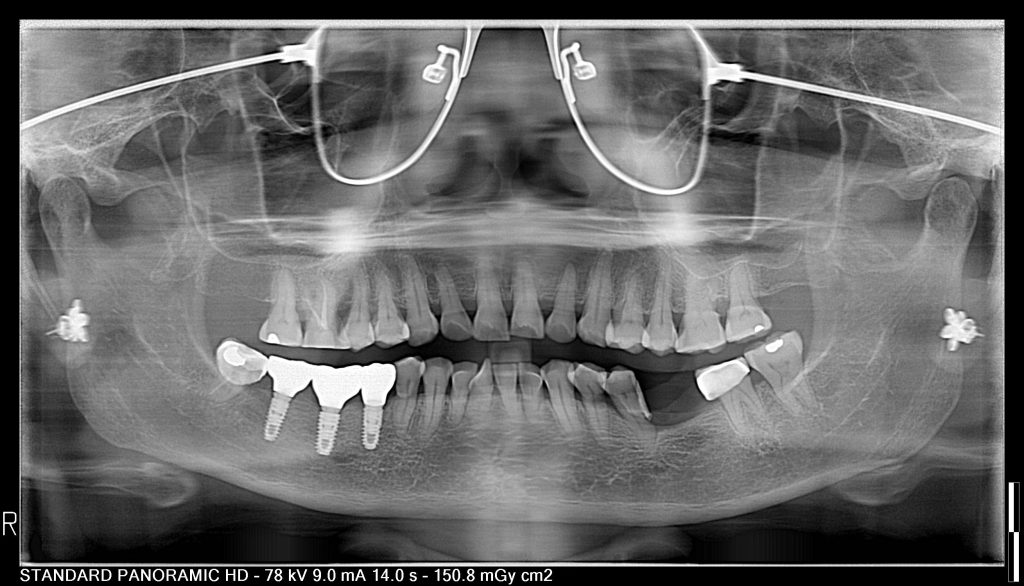

A panoramic X-ray is a type of X-ray imaging used in dentistry to capture a comprehensive image of a patient’s mouth, including the teeth, upper and lower jaws, sinuses, and surrounding structures and tissues. The result of a panoramic X-ray is a two-dimensional image that encompasses the entire mouth area in a single shot.

- Diagnosing Dental and Jaw Problems: Panoramic X-rays are very useful for detecting issues such as impacted teeth, infections, cysts, tumors, and disorders of the jaw joint (temporomandibular joint).

- Treatment Planning: The panoramic image helps dentists plan orthodontic treatments (such as braces), wisdom teeth extractions, or dental implant placements.

- Detecting Hidden Issues: A panoramic X-ray can reveal problems in areas that are difficult to reach or not visible with a regular clinical examination, such as within the jawbone or sinuses.

- Comprehensive Examination: Because it covers the entire mouth area, a panoramic X-ray provides a more complete view compared to standard dental X-rays (bitewing or periapical), which only show specific parts of the mouth.